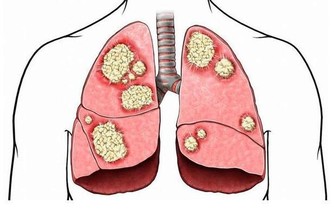

使得各種慢性病、癡呆、肥胖、肝病、癌症等情況紛紛出現,嚴重的甚至危及生命!把酸排出來,把命鹼回來!

日本著名醫學博士柳澤文找100個癌症患者抽血檢查,

結果100個癌症患者的血液都呈酸性,也就是酸性體質。酸性體質有哪些危害?